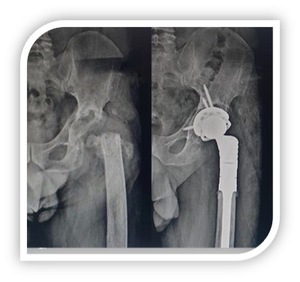

Forty-four patients were included in the study. At 5 years follow-up (2.1 to 6.5), 39 patients, 23 female and 16 males, were alive. Four patients died for non-related surgery causes; one was lost at follow up. The etiopathogenesis was represented by periprosthetic fractures (6), periprosthetic osteolysis (15), revision implant failures for recalcitrant infections (18).(Fig 1, 2) The average age was 69 years (47 to 78).